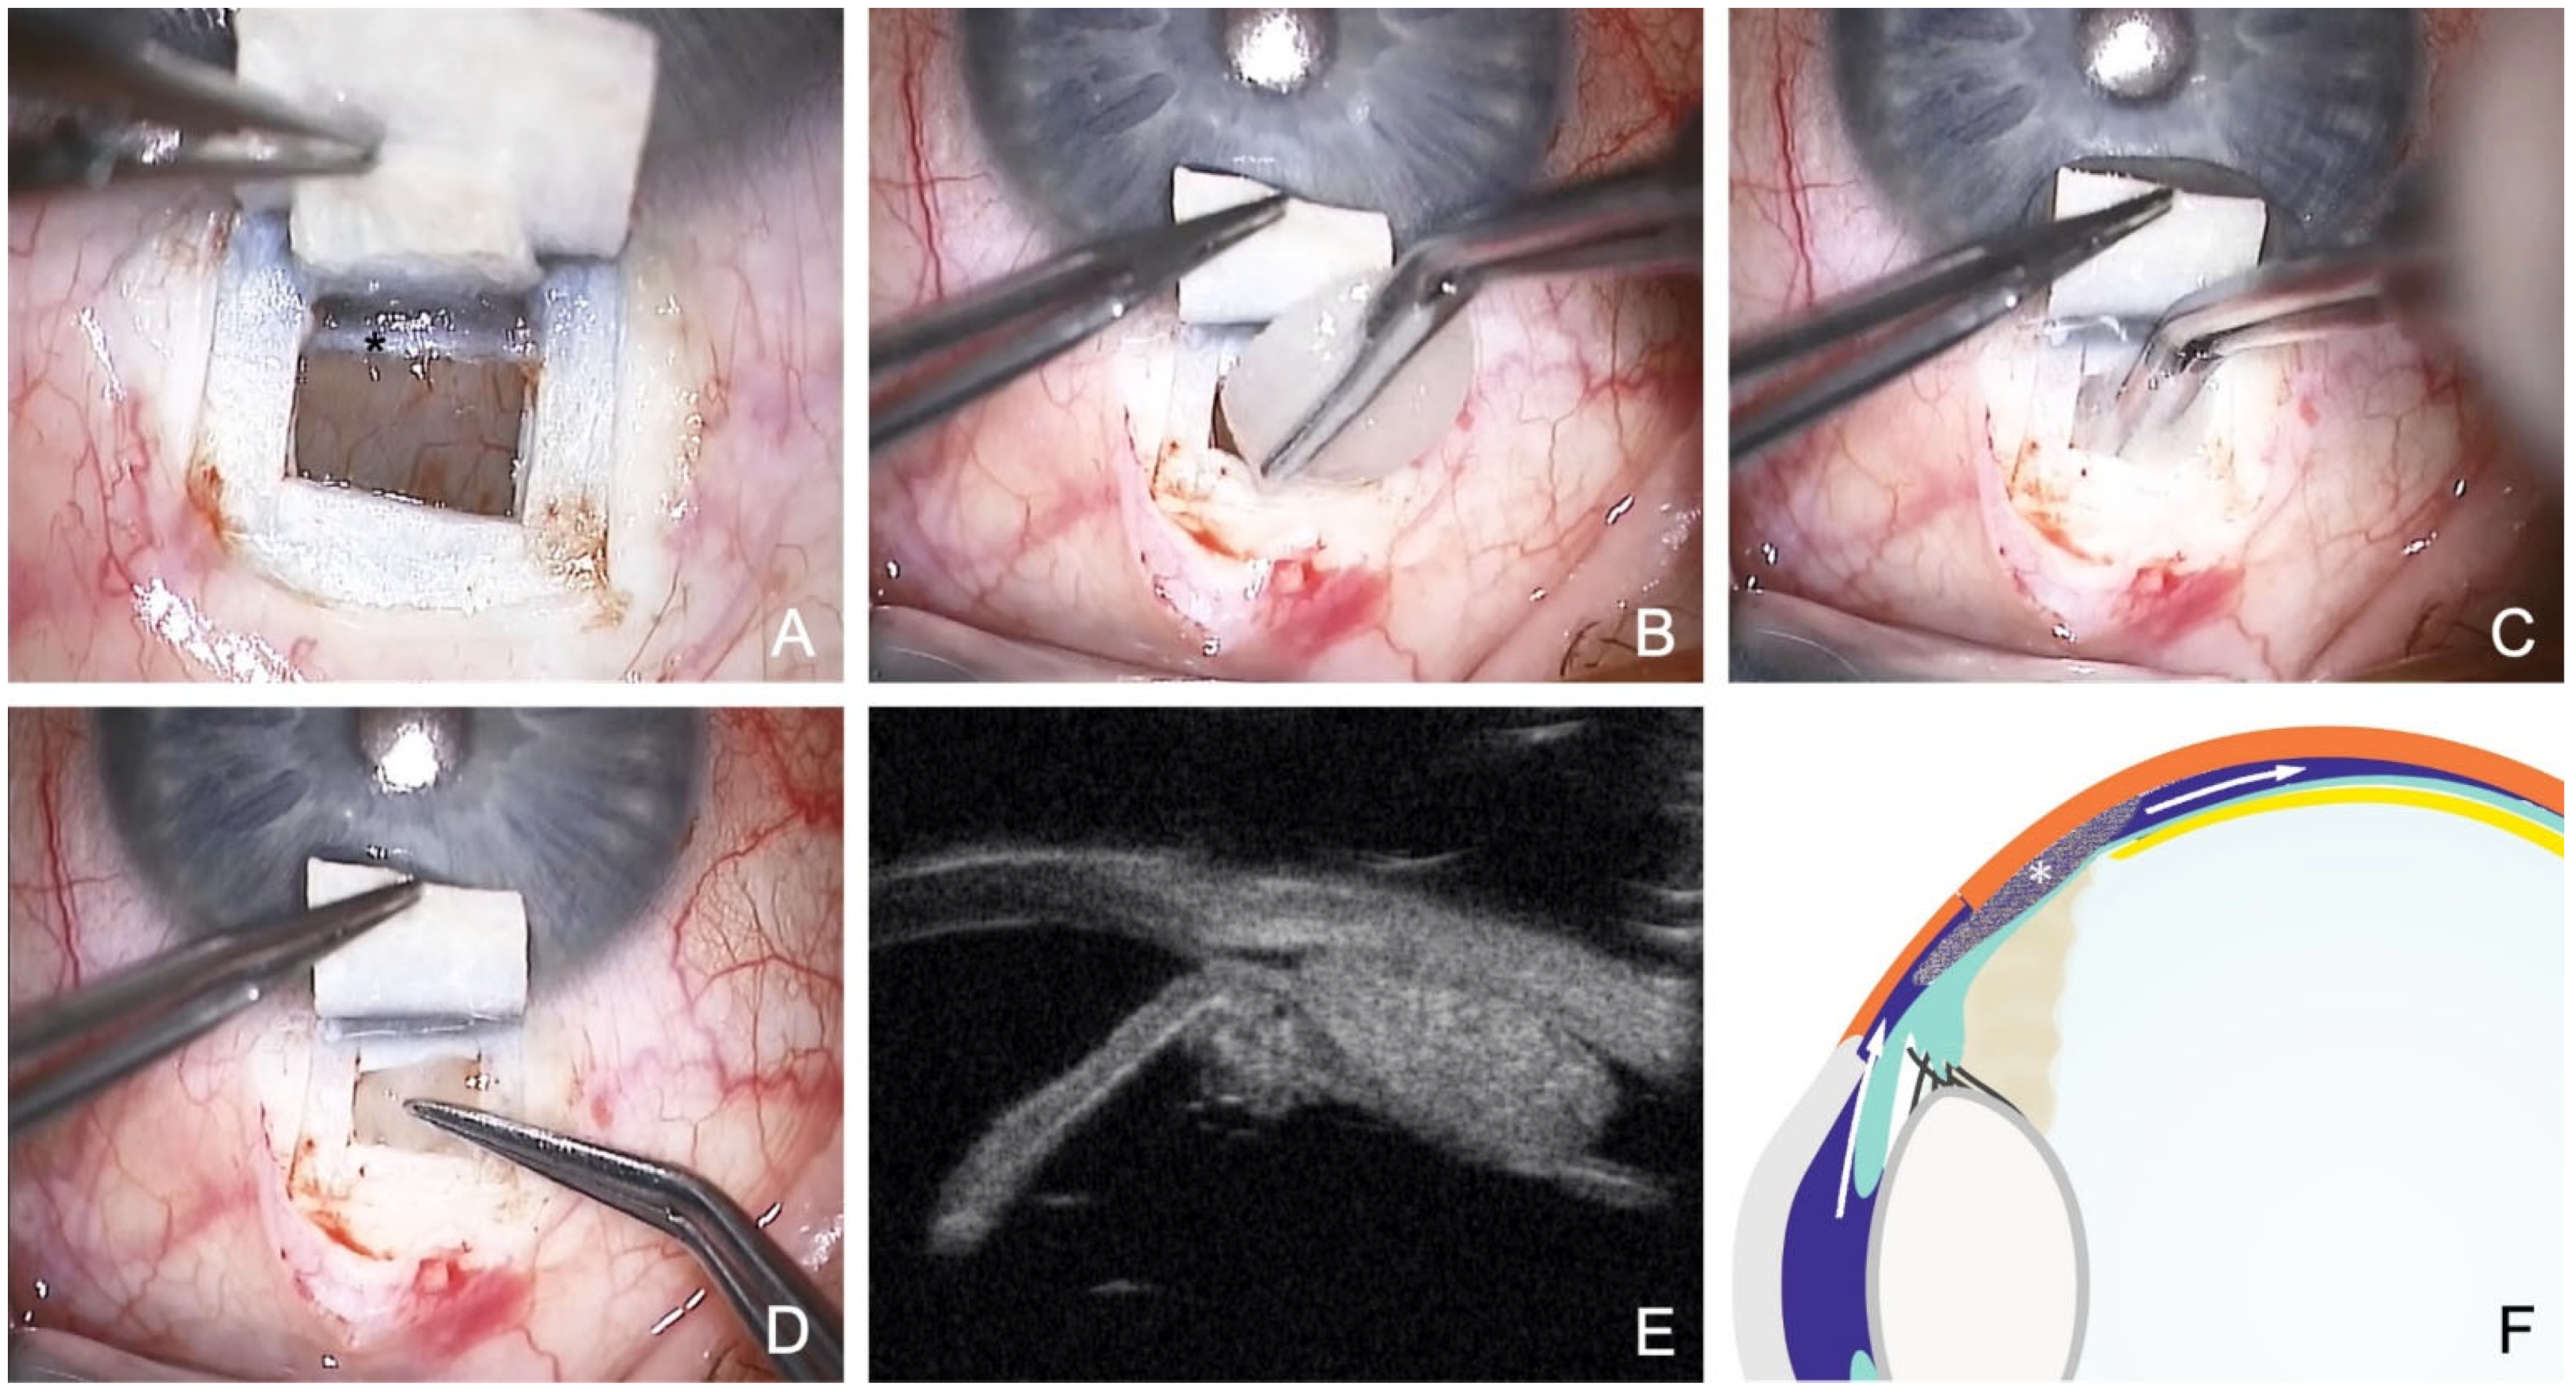

- Szurman, P.; Januschowski, K.; Boden, K.T.; Szurman, G.B. A modified scleral dissection technique with suprachoroidal drainage for canaloplasty. Graefes Arch. Clin. Exp. Ophthalmol. 2015, 254, 351–354. [Google Scholar] [CrossRef]